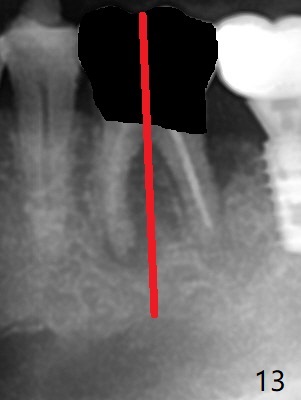

Venopuncture is conducted (Fig.1) for PRF and sticky bone (cortical chip and .5 cc ß-TCP). After use of proximators at #19, cowhorn forceps are applied, resulting in metal crown dislodgement. Since there is distal bone loss, distal socket sheath is contemplated. The tooth is sectioned. When an elevator is inserted between the roots, the distal root is loosened first. The 2 roots are removed, revealing a rounded end septum (Fig.2 S) and a larger distal socket. To avoid osteotomy deviation over the septum, a 12 mm bone trimmer is used, followed by point drill (Fig.3 *). But the lower half of the implant is deviated mesial (Fig.4) with decreased torque (~ 10 Ncm). To overcome this misfortune, the roots should not be removed until osteotomy is finished. Dual zones of bone graft is conducted. Sticky bone is placed until the plateau of the implant with a healing screw in place (Fig.4 * (bone zone)). After placement of a pair abutment, the same bone graft is packed until the margin of the abutment (Fig.5 * (soft tissue zone)). An immediate provisional is fabricated to close the socket with a piece of PRF as well. Fig.6-11 explains why the lower half of the implant deviates to the mesial socket, while Fig.12-16 illustrates how to prevent the deviation. After extraction of #19 (Fig.6,7), the crest of the septum is flattened (Fig.8 arrowhead) to prevent the initial deviation (Fig.9 red line). When a drill reaches a space (a socket, mesial in this case), the drill is deflected to the least resistant area (Fig.10 a bent red line), leading to the implant deviation apically (Fig.11 green). To prevent the apical deviation, therefore, the roots of the affected tooth is temporarily not removed (Fig.12). The osteotomy should not deviates with surgical guide because of similar density between the tooth and the bone (Fig.13). When the osteotomy is finished (Fig.14), the roots are extracted (Fig.15). The implant to be placed should not have deviation (Fig.16 green). The papillae are maintained by the immediate provisional 11 days postop (Fig.17). The incompletely seated abutment at #18 (Fig.5 <) is reseated completely 6 months postop (Fig.18). Crestal bone forms distal to #19 implant. There is no bone loss 4 months and 3 years 1 month post cementation at #19 and 18, respectively (Fig.19,20).